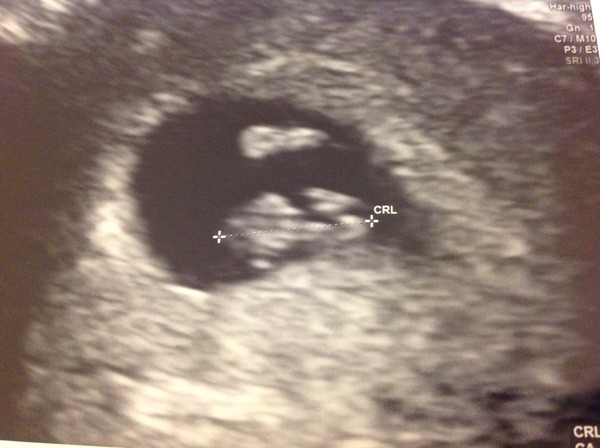

Just wanted to share my scan with you all! 7w2 she dated at which is bang on what I thought (and way off the midwives little wheel thing) blob at the top is the yolk sac and blob at the bottom is the prawn baby-head probably on the left as it's bigger and the heart was nearer it.

Plus she confirmed the follicle I ovulated on was on my left ovary-which is where I thought I felt an ovulation 'pop' on the day I ovulated! The story comes together Smile